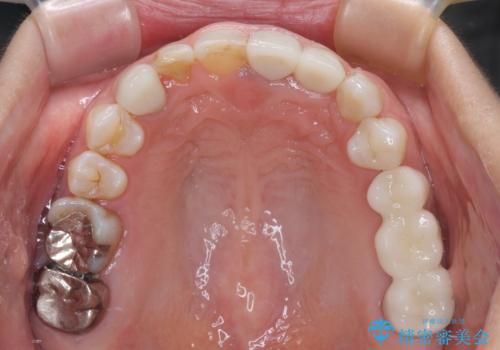

咬み合わせ改善のため、前歯の過剰歯を抜去し、ワイヤー矯正にて歯列と咬み合わせることとしました。

左上の奥歯のブリッジや前歯のセラミッククラウンはいったん除去し、矯正治療後に補綴治療を行うこととしました。

また、右下の抜歯が必要な奥歯は、矯正治療の途中でインプラントを埋入し、矯正治療後に上顎と合わせて補綴治療を行うこととしました。

上下非接触の咬み合わせは、舌突出癖によるところが大きく、トレーニングを行いながら治療を進めていきました。